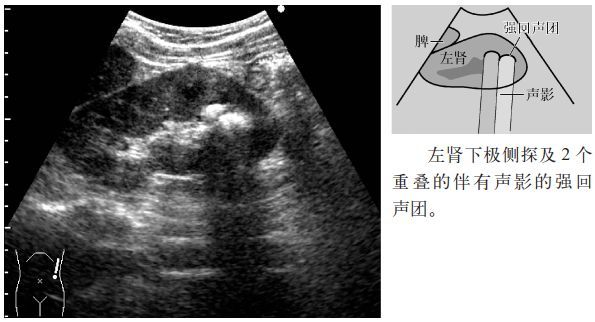

临床必备肾结石输尿管结石超声表现一览